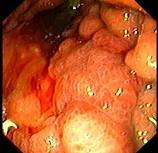

问题 男性患者,45岁,平素身体健康,近2个月出现上腹饱胀不适,偶有隐痛,伴纳差,近2天有黑粪,胃镜如图。关于本病,下列说法正确的有 ( )

选项 A、处于进展期 B、应马上手术治疗 C、可诊断为胃间质瘤 D、处于早期 E、可诊断为胃癌

答案 ABE